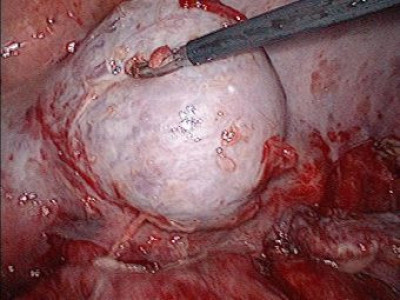

Derrame pleural derecho mas tumor de mediastino posterior